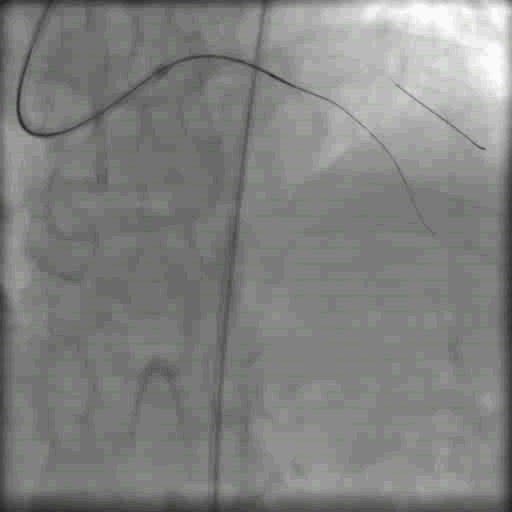

更换指引导丝GAIA2穿刺近端纤维帽,缓慢前行无阻力,对侧造影偏离LAD主支方向

李妍教授点评:

术者使用AWE技术,导丝升级至Gaia2,远端不在预计的LAD走形方向,没有贸然推进微导管或球囊扩张是正确的。但造影时间略短,没有充分显影血管远端,走形上判断应该进入了对角支,所以不宜轻易回撤导丝放弃,可适当回撤近端微导管,再次造影判断远端是否在对角支里,一旦确认,应当更换软导丝先保护对角支再进行后续操作。

调整指引导丝GAIA2至LAD远端,对侧造影在真腔